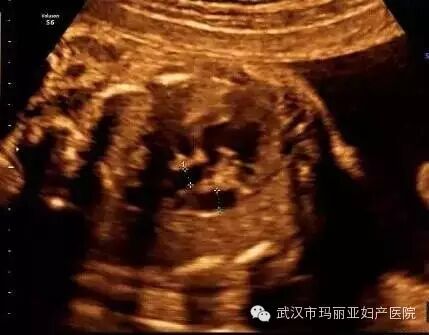

武汉玛丽亚妇产医院引进的世界领先的美国GE-E8四维彩超设备室目前世界上最先进、分辨率最高的彩色超声设备,具有即时立体成像、清晰准确的特点。

它能够多方位、多角度地观察宫内胎儿的生长发育情况,为早期诊断胎儿先天性体表畸形和发育异常提供科学依据。还能对胎儿的体表进行检查,如唇裂、脊柱裂、大脑、肾、 骨骼发育不良等,以便尽早的进行治疗。

玛丽亚美国GE-E8四维彩超排畸成功案例